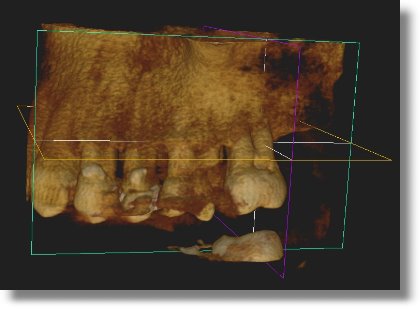

3D-Darstellung in der Richtung des obigen Röntgenbildes

3D-Darstellung in der Ansicht von oben

Dreht man nun das Bild um 90° ist ein ausgedehnter Knochendefekt am hinteren Seitenzahn zu erkennen.